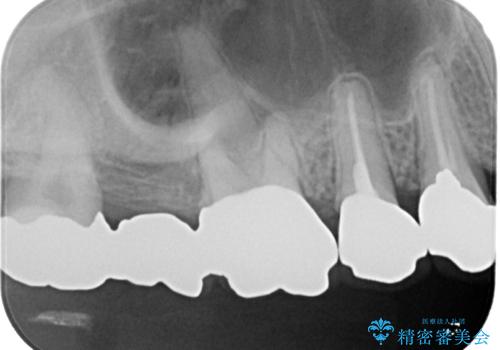

前歯に変色が起こる場合、神経組織の失活により引き起こる可能性が高いため、診察を行ったところ、根尖部の病変や叩いたときの痛みなどが認められました。

まずは根管治療を行い、痛みの消退を確認してからオールセラミッククラウンによる補綴治療を行うこととしました。

前歯に痛みがあるという実感はなかったそうですが、診察で叩いたときの痛みを感じた際、今までに同様の痛みや違和感を感じたことがあったとのことでした。

初回の根管治療で痛みや違和感は消退したため、その後は速やかに補綴治療を行いました。